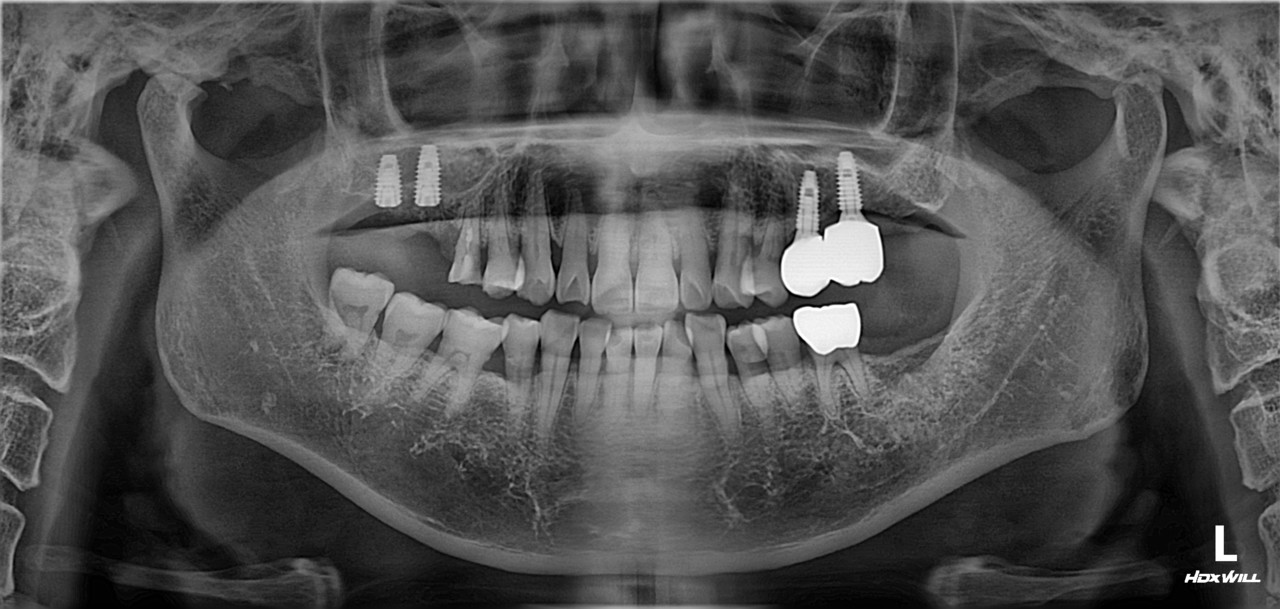

상악동 거상술 및 임플란트 식립

치료 기간 2023. 12. 21(치료 당일)

아래 치료는 상악동 거상술 및 임플란트 식립에 대한

치료 당일에 대한 설명입니다.

우측 상악 잔존골이 얼마 없는 난이도가 있는 수술이지만, 참조은치과에서는 수술시간이 15분 정도 소요되었습니다. 근육주사를 이용하여 붓기 조절 및 염증 조절도 시행하였습니다.

참조은치과 전속 기공사 선생님들이 상주하여 모든 임플란트를 지르코니아로 제작 중이며, 인접면 처리 및 교합조정이 바로 가능합니다.

아래 치료는 상악동 거상술 및 임플란트 식립에 대한 치료 당일에 대한 설명입니다.

우측 상악 잔존골이 얼마 없는 난이도가 있는 수술이지만, 참조은치과에서는 수술시간이 15분 정도 소요되었습니다.

근육주사를 이용하여 붓기 조절 및 염증 조절도 시행하였습니다.

참조은치과 전속 기공사 선생님들이 상주하여

모든 임플란트를 지르코니아로 제작 중이며, 인접면 처리 및 교합조정이 바로 가능합니다.